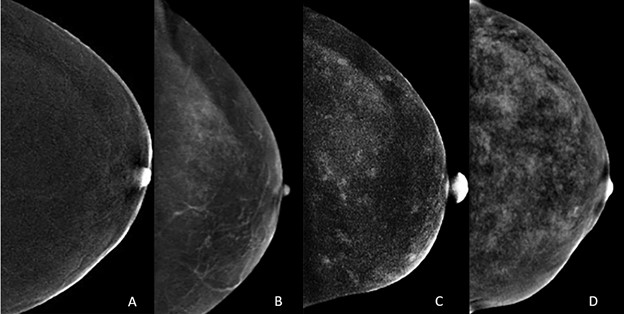

We will also discuss background parenchymal enhancement (BPE) in CEM image interpretation. Similar to breast tissue density of mammography, increased BPE may both mask and mimic cancer on CEM. As on MRI, there are four categories of BPE (Fig. 1), and multiple factors are associated with increased BPE [4]. We will present the audience with a range of appearances for normal BPE on CEM.